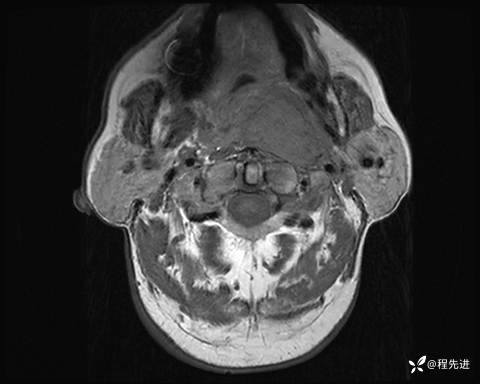

MRI平扫+增强:

T2压脂: